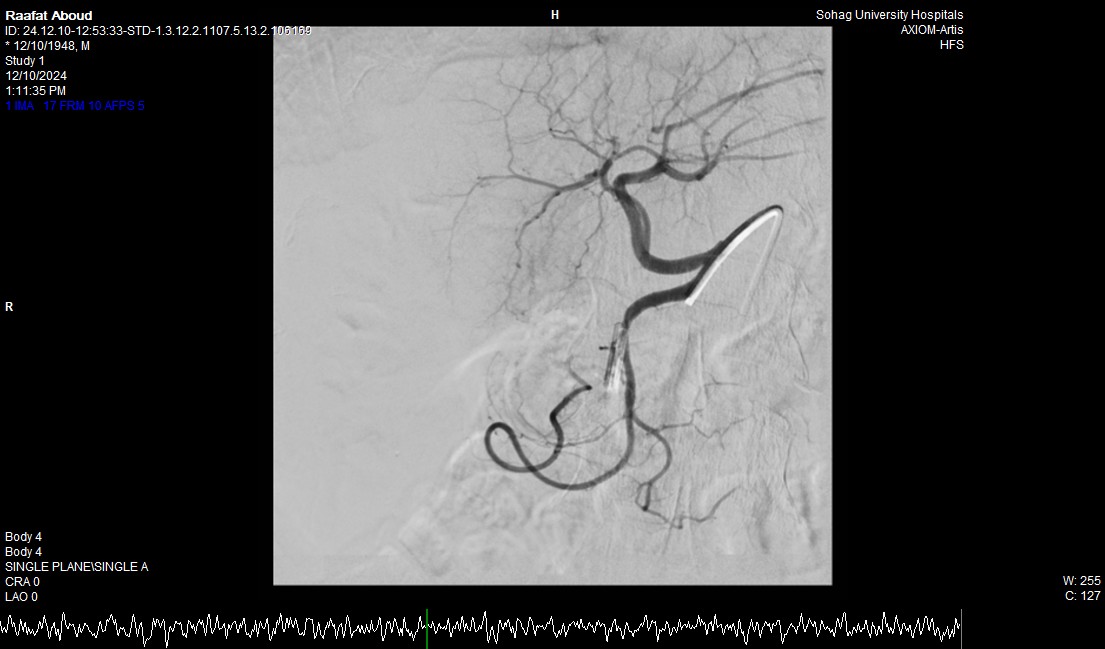

صرح الدكتور حسان النعماني رئيس جامعة سوهاج ان فريق طبي بوحدة الجهاز الهضمي والكبد بقسم الباطنة العامة ووحدة الاشعة التداخلية بقسم الاشعة نجح في انقاذ حياه مريض يبلغ من العمر ٧٥ عاماً له تاريخ مرضي ويعاني بقصور بوظائف الكلي وتليف بالكبد، حيث نجح الفريق في ايقاف نزف شرياني حاد من خلال إجراء التدخل السريع بإستخدام المنظار والقسطره الشريانيه العلاجيه بالاشعة التداخلية، مثمناً دور المستشفيات الجامعية في خدمة المرضي وما تمتلكه من الكوادر الطبية ذوي الخبرات التي تؤهلها للتعامل مع مثل هذه الحالات الطارئة باحترافية ومهارة فائقة.

وأضاف الدكتور أحمد كمال المدير التنفيذي للمستشفيات الجامعية انه بعد اجراء الفحوصات للمريض تبين وجود قرحة كبيرة بالاثني عشر وشريان نازف، حيث نجح الفريق في التحكم المبدئي بالنزيف عن طريق تركيب مشبك معدني بالمنظار وحقن للقرحة النازفة، ثم تم استدعاء فريق أطباء وحدة الاشعة التداخلية علي الفور وتم عمل غلق للشريان النازف بشكل عاجل من خلال جهاز القسطرة.

وذكر الدكتور نايل عبد الحميد رئيس قسم امراض الباطنه ان هذا التدخل الطارئ لايقاف النزيف من خلال المنظار او من خلال غلق الشريان بواسطه الاشعة التداخلية جنب المريض من التعرض للحل الجراحي في هذا العمر، مشيراً الي ان المريض الآن في حالة مستقرة حيوياً وتوقف تام للنزيف وتحسن لوظائف الكلي والكبد وتم خروجه من وحدة الرعاية المتوسطة للمتابعة بالقسم الداخلي

وأوضح الدكتور محمد زاكي رئيس قسم الأشعة أن مثل هذه الحالات تعد من الطوارئ الطبية الخطيرة والتي تستوجب عمل قسطره شريانية عاجلة لغلق الشرايين النازفه مشيراً أن وحدة الأشعة التداخلية تم تزويدها بجهاز أشعه محوري متقدم لاجراء مثل هذه الحالات، وأن هذا النجاح هو نتيجة لتعاون أقسام المستشفي مع وحدة الأشعة التداخليه لتقديم خدمة مميزه للمرضي.